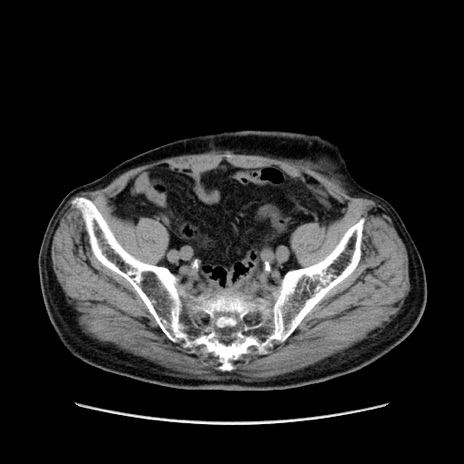

症例24(横断像)

【症例】80歳代男性

【主訴】左側腹部痛、嘔吐

【現病歴】本日早朝より左腹部に痛みあり。昼頃嘔吐認めたため、救急要請。

【既往歴】直腸癌(Mile手術)、胆摘

【身体所見】意識清明、BT 35.9℃、BP 221/93mmHg、SpO2 97%(RA) 、腹部:左ストーマ周囲に限局性の腹部膨隆あり。 膨隆部自発痛・圧痛あり・軟。

【データ】WBC 7700、CRP 0.09